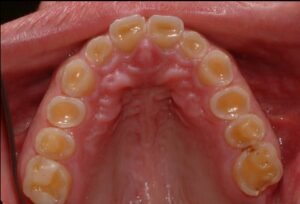

Si el bruxismo se mantiene en el tiempo puede generar sobrecarga de la ATM, inflamación muscular crónica, desgaste dental progresivo, fracturas dentarias, alteraciones posturales y dolor

orofacial persistente. Por eso el diagnóstico temprano es fundamental.